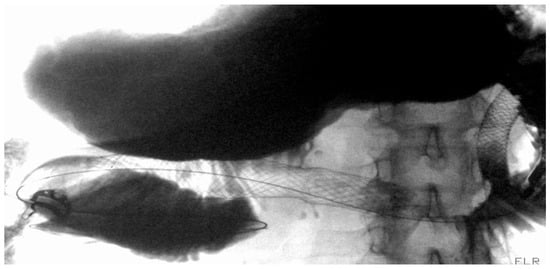

4. Gastroduodenal Tract—Gastric Outlet Obstruction

4.1.1. Role of Stent

Indications and Mechanism of Action

Efficacy and Adverse Events